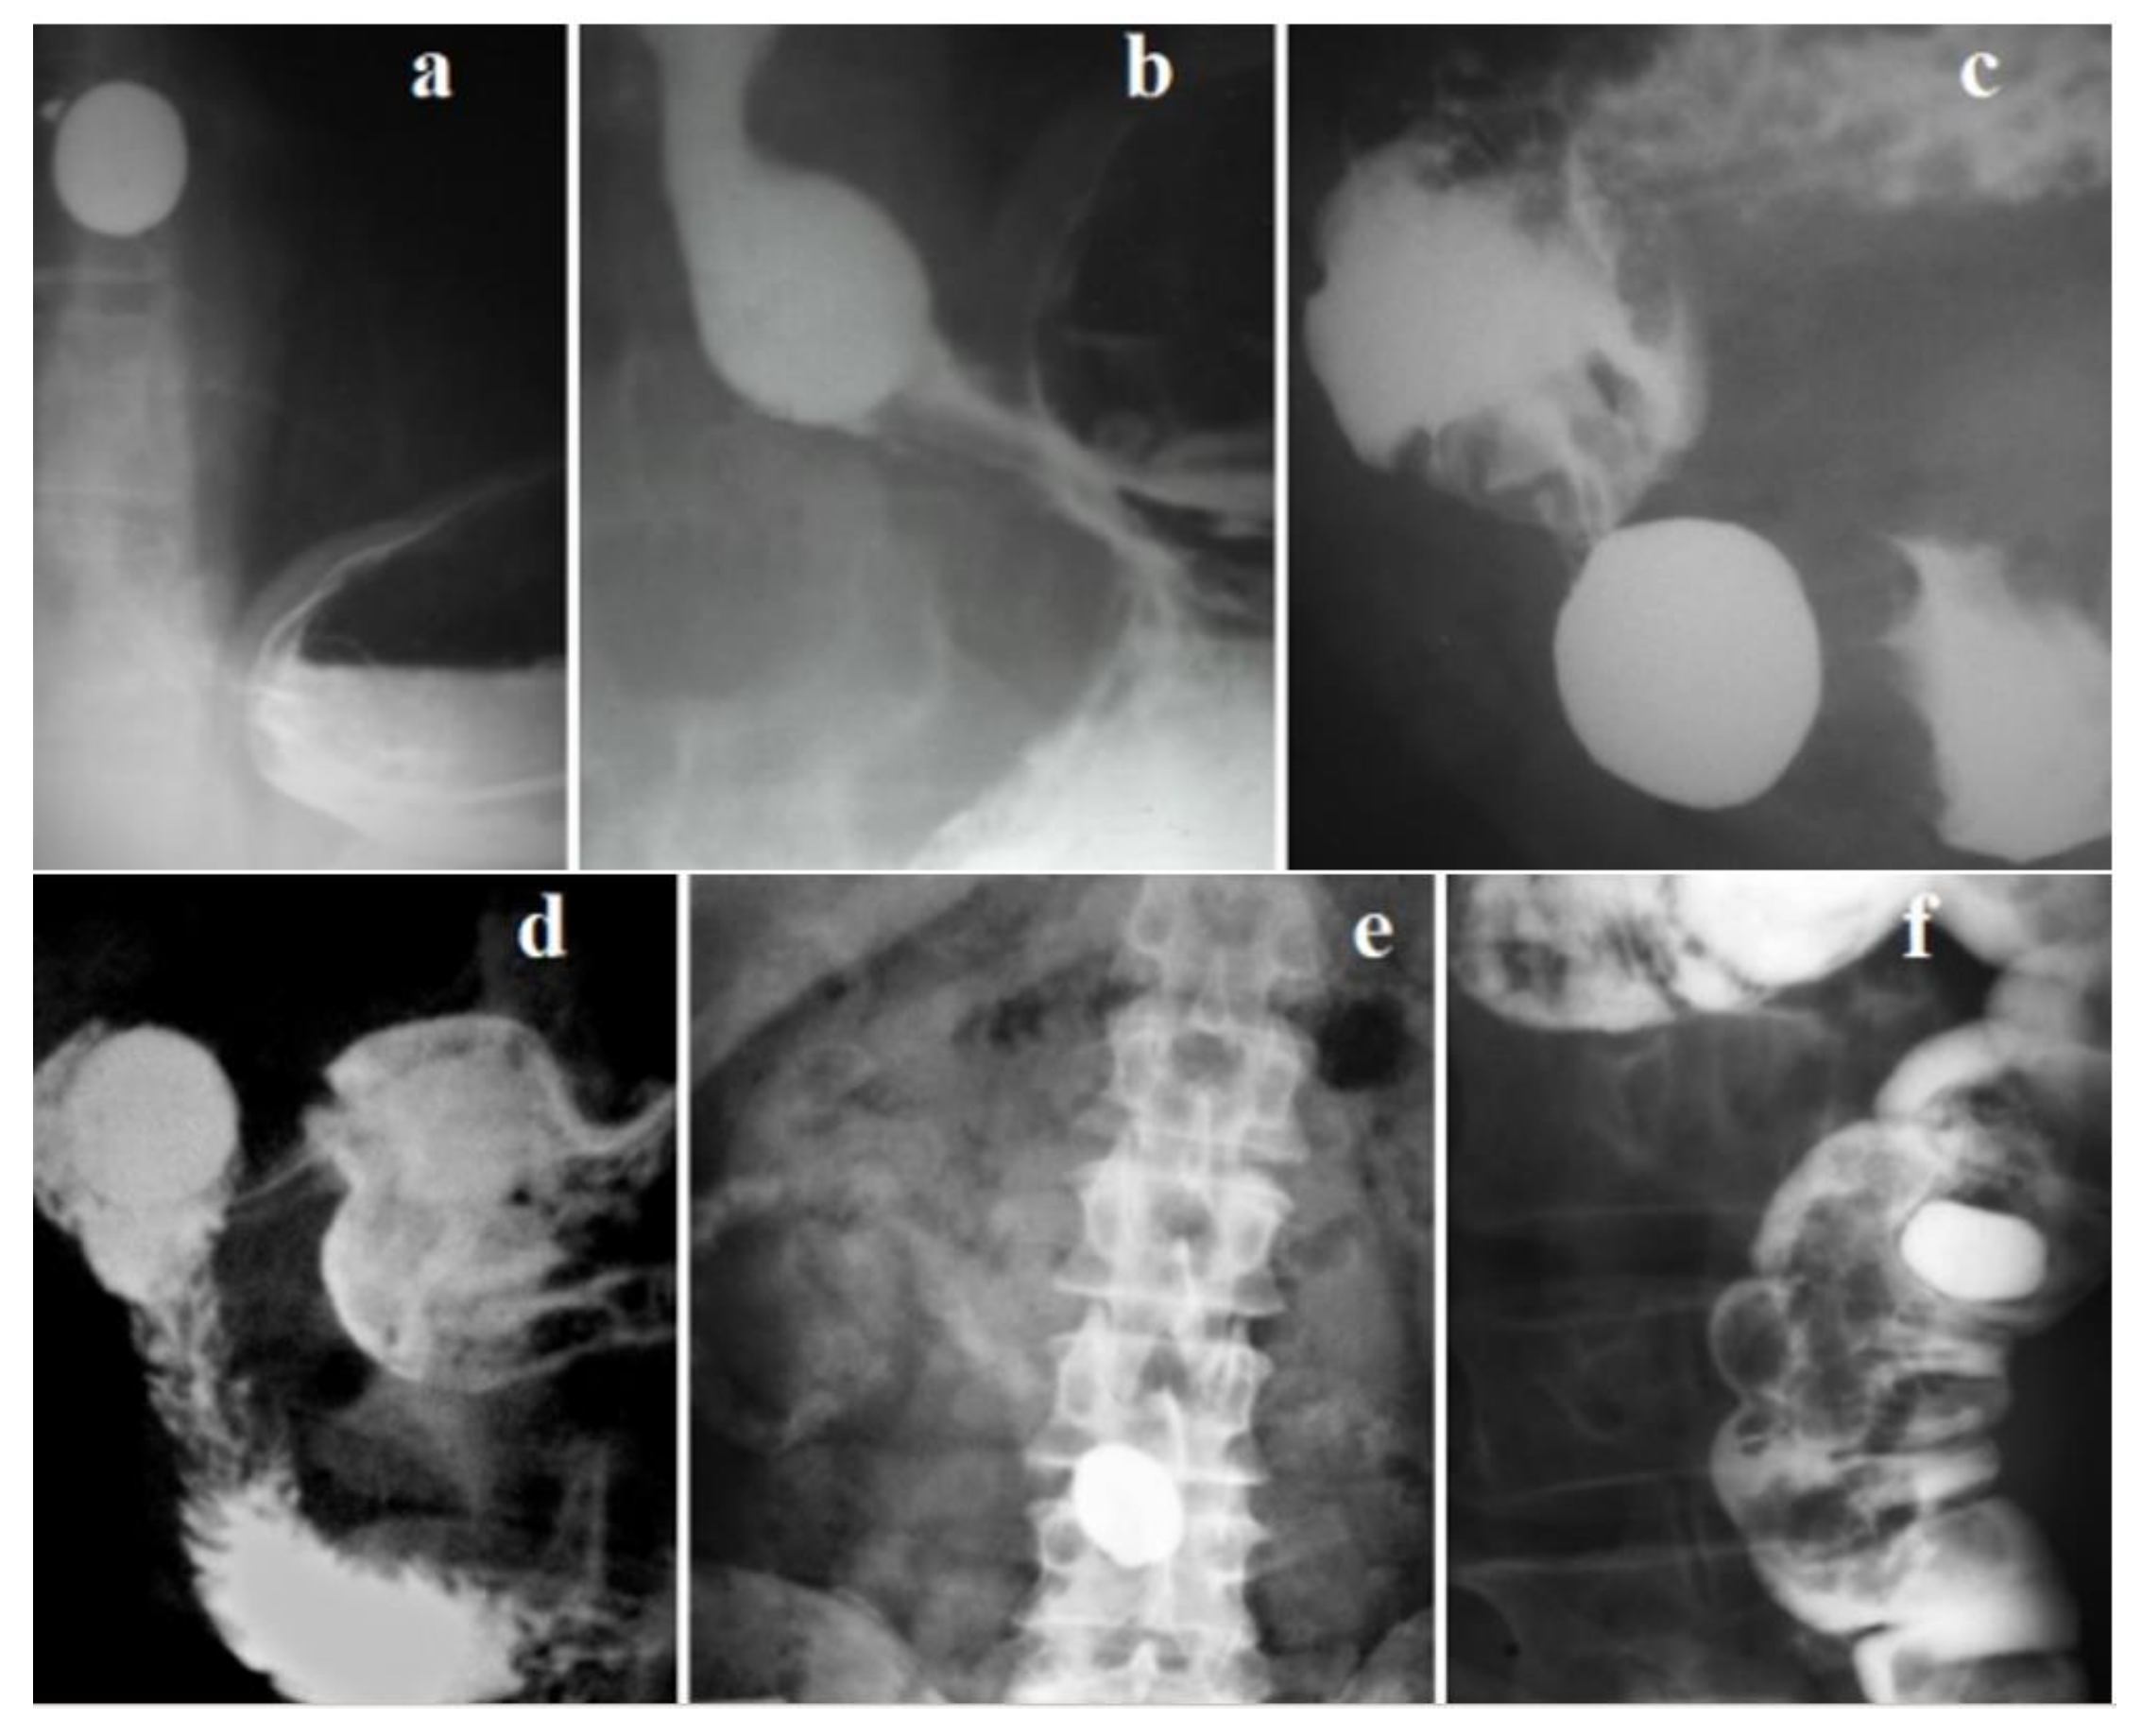

3. Hiatal hernia: myth or reality?

- A hiatal hernia is a phrenic ampulla, regardless of its size. It indicates a more severe form of GERD.

- I have proven the appearance of a functional sphincter in GERD. During eating thick foods, its contraction closes the proximal lumen of the ampulla, helping to create high pressure in the ampulla to inject the bolus into the stomach. It also contracts to prevent reflux above the ampulla. This proximal sphincter (PS) is 5–7 cm long [42]. Over time, it turns into a fibrous ring of different diameters. In some patients, PS turns into a narrow fibrous ring that impairs passage along the esophagus. This is the so-called Schatzki ring [42,50].